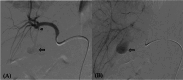

The pseudoaneurysms of the cystic artery (CAP) are very uncommon. They usually develop as a result of an acute cholecystitis or after a cholecystectomy. Among the complications, we can find hemorrhaging, biliary blockage, and haemobilia. Limited understanding of the illness makes managing specific cases difficult. We describe a case of a cystic artery pseudoaneurysm complicating an acute cholecystitis that was successfully treated by transcatheter arterial embolization.